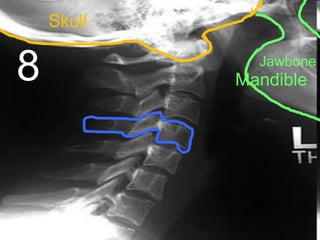

Skull

8

Jawbone

Mandible

Vertebrae